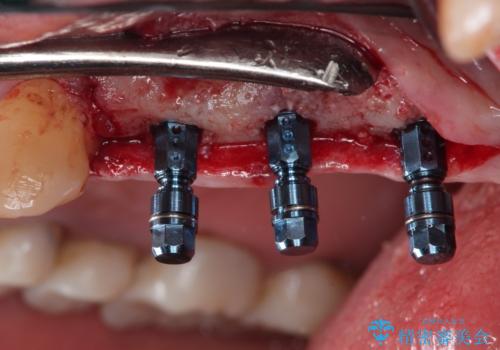

- 定期検診にて不良補綴物、及び虫歯を認めオールセラミッククラウンにて治療を行いました。

右上第二小臼歯はカリエス除去中に露髄を認め、部分的断髄法にて歯髄を保存しております。